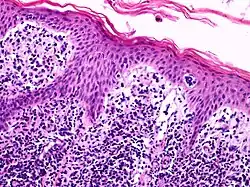

A histological view of Lutzner cells surrounded by erythrocytes in a blood smear.